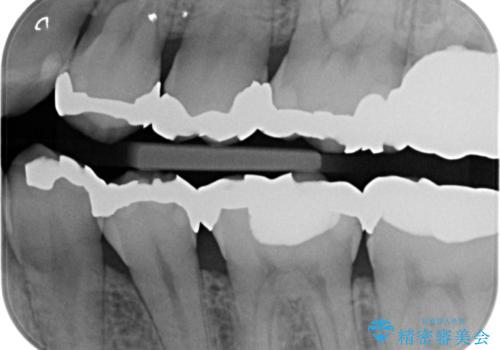

銀歯を外して被せ物の予定でしたが歯の高さが低く取れやすい被せ物になってしまうため歯の高さを変える手術を行いました。

まずはメタルを全て外し仮歯にして、手前のメタルインレーは手術前にセラミックインレーの治療を行いました。

治療後の写真は2週間後の写真です。歯茎の治癒が完全に治るのは半年くらいかかるので半年後に最終的な被せ物を入れる予定です。